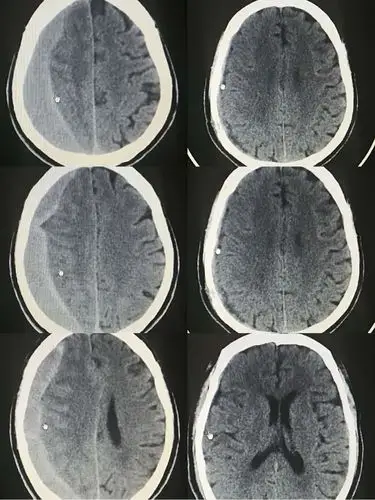

机化性慢性硬膜下血肿一例

双侧慢性硬膜下血肿病例分享

慢性硬膜下血肿